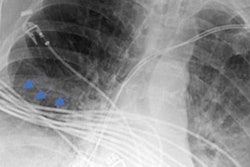

Right-sided pneumothorax (black arrow) reported by both the resident and the attending radiologist. Image courtesy of Cureus.According to the results, pneumothorax was reported by residents in 164 (94.25%) cases, while the attending radiologist reported it in 167 (96%) cases. The remaining 4% of cases were ultimately diagnosed on a chest CT scan. Concordance between the on-call residents and attending radiologists was 92.5% (p = 0.008), the researchers reported.